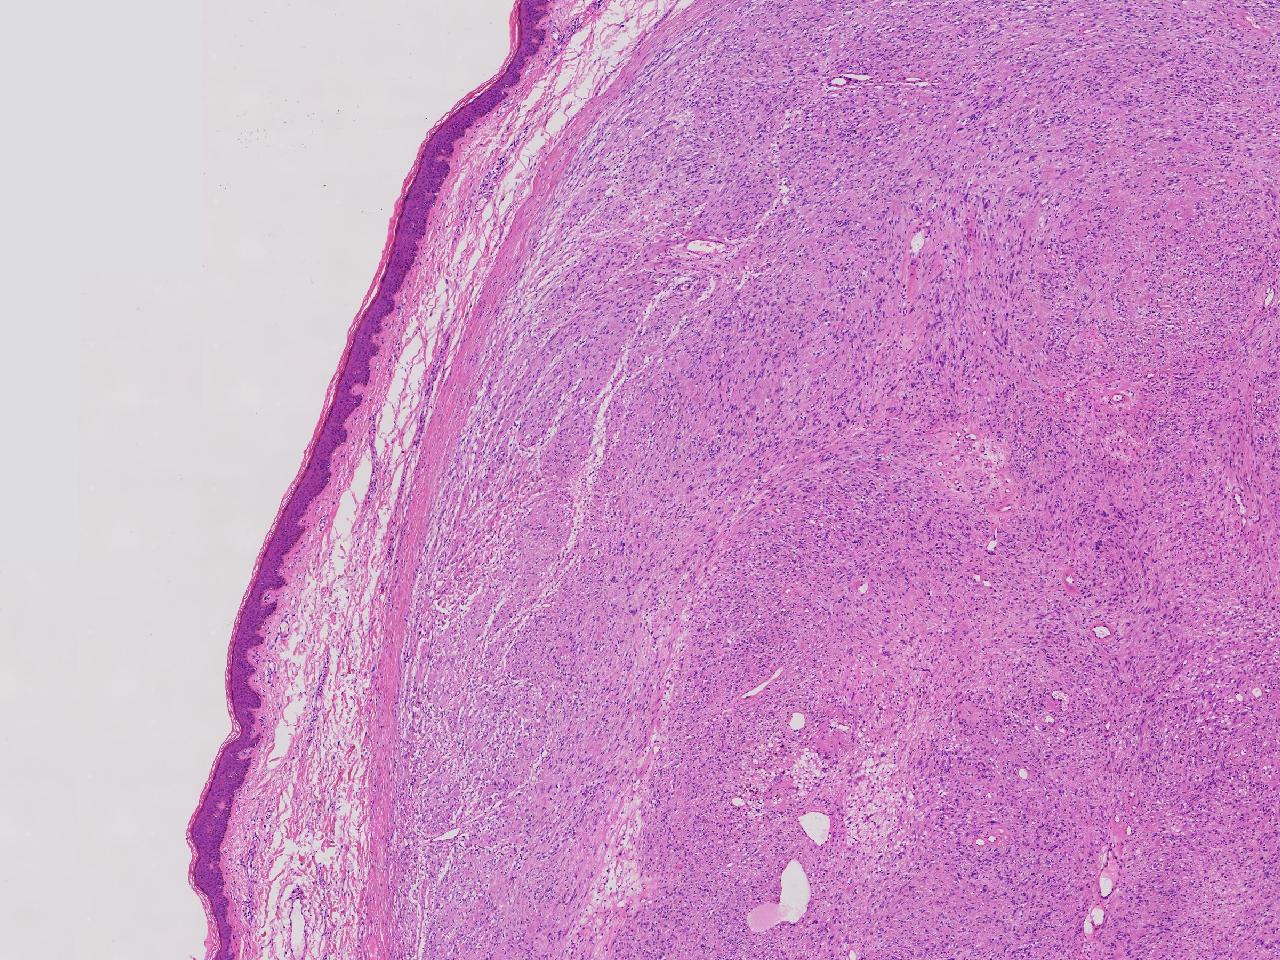

血管平滑肌瘤? 其他?

大体所见

卵圆形肿物一个,直径1.6厘米,上附皮肤。肿物切面灰黄实性,质中等。

考虑:结节性筋膜炎

完整的包膜。 首先还是考虑神经鞘。

神经鞘瘤。

建议除外平滑肌瘤,做IHC是更好的鉴别方式